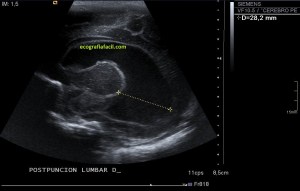

En la imagen 3 ves una imagen de un lipoma, mide 7 cms, la huella de la sonda mide 5cms, la «panoramic view» posee una regla centimetrada que sigue el contorno de la imagen, justo en la profundidad de la misma y lo marca la flecha amarilla. La profundidad la marca la flecha roja y la flecha blanca marca el rango centimetral de los 5cms, fíjate que la línea blanca es ligeramente mayor cada 5 cms. Sirve de referencia, como en la imagen 4 donde ves una colección en el glúteo de más de 10 cms.